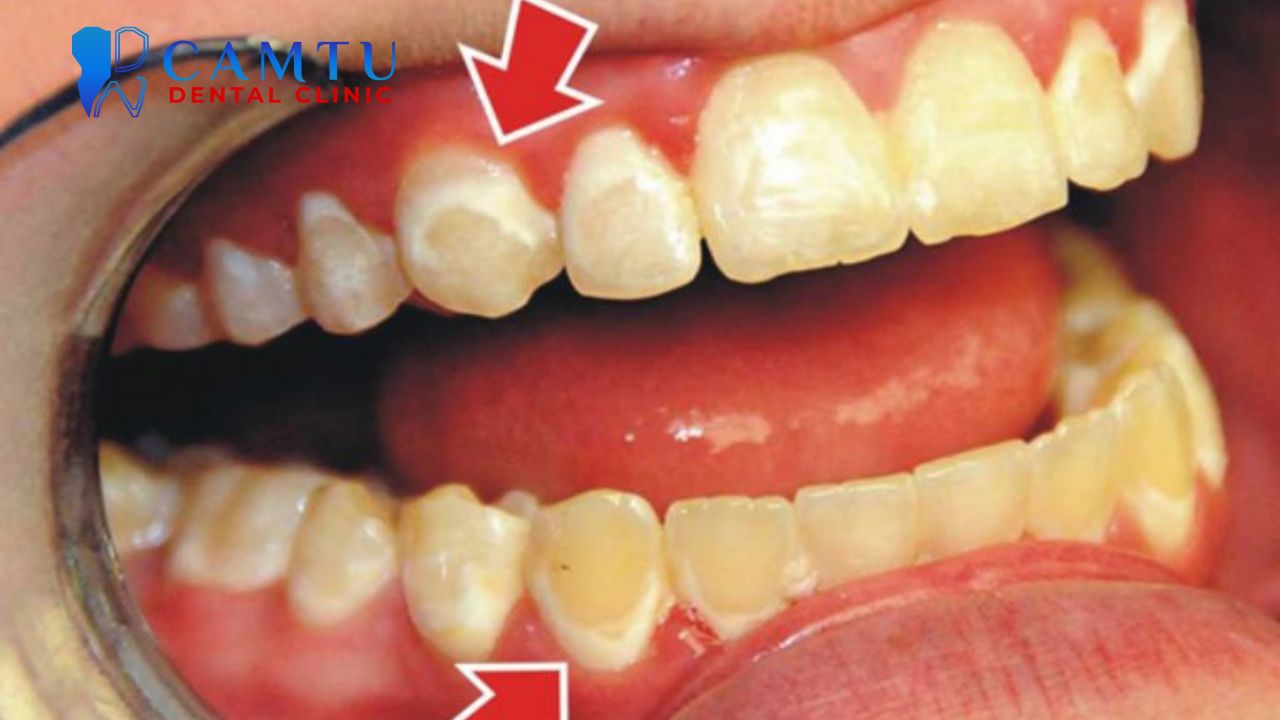

Viêm lợi và viêm nha chu khi mang thai

Viêm lợi thai kỳ thường xuất hiện từ tam cá nguyệt thứ hai. Nguyên nhân chính là do nội tiết tố tăng cao làm lợi nhạy cảm hơn với vi khuẩn mảng bám. Dấu hiệu dễ nhận thấy là lợi sưng, đỏ và chảy máu khi chải răng.

Nếu viêm lợi không được kiểm soát, tình trạng này có thể tiến triển thành viêm nha chu. Nhiều nghiên cứu cho thấy viêm nha chu ở mẹ bầu có liên quan đến nguy cơ sinh non và trẻ nhẹ cân. Do đó, việc chăm sóc răng miệng cho phụ nữ mang thai phải cần được quan tâm đặc biệt.